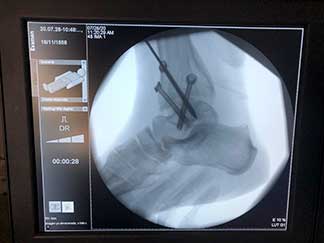

Radiografía de una artrodesis de tobillo en futbolista